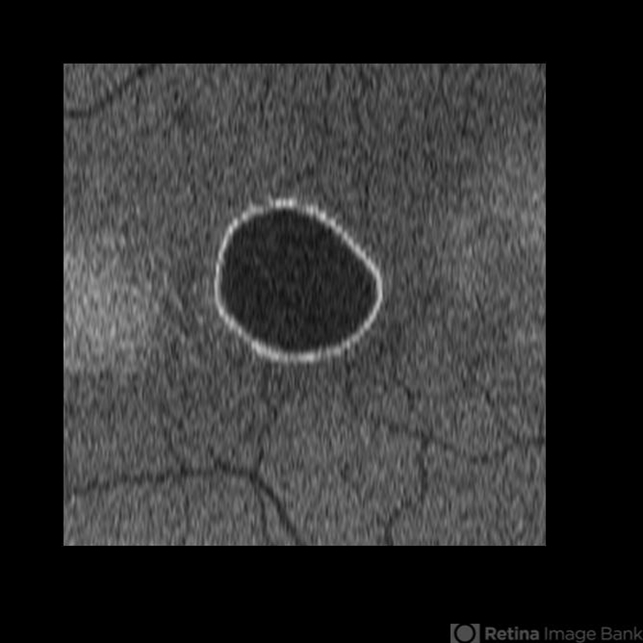

- idiopathic serous detachment of the retinal pigment epithelium

- Kristin Konecki, OcuSight Eye Care Center, Rochester, NY

Scanning laser ophthalmoscope

Cirrus - Description

- C-Scan